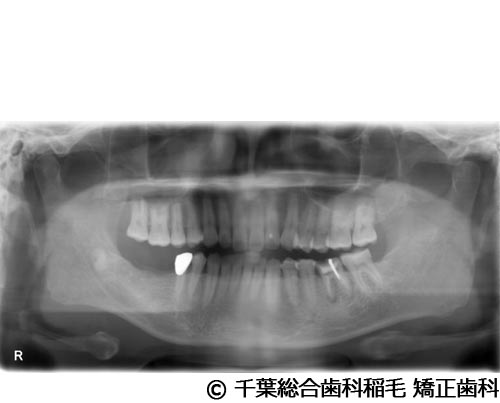

【症例2】下顎大臼歯2本インプラント埋入手術

- 治療前

- 治療後

- 治療名

- 下顎大臼歯2本インプラント埋入手術

- 費用

- 950,000円(税込)

- 期間

- 11ヵ月

治療内容

-

患者様の症状

歯茎の腫れと痛みが主訴でご来院されました。

治療法

右下第一、第二大臼歯は重度の歯周病だったため、保存が難しく、抜歯となりました。

義歯とインプラントそれぞれのメリットデメリットをお話しさせていただき、インプラントでの治療を選択されました。 -

治療結果

お痛みや腫れも和らぎ、現在も定期検診で拝見させていただいています。

※治療結果は患者様によって個人差があります。